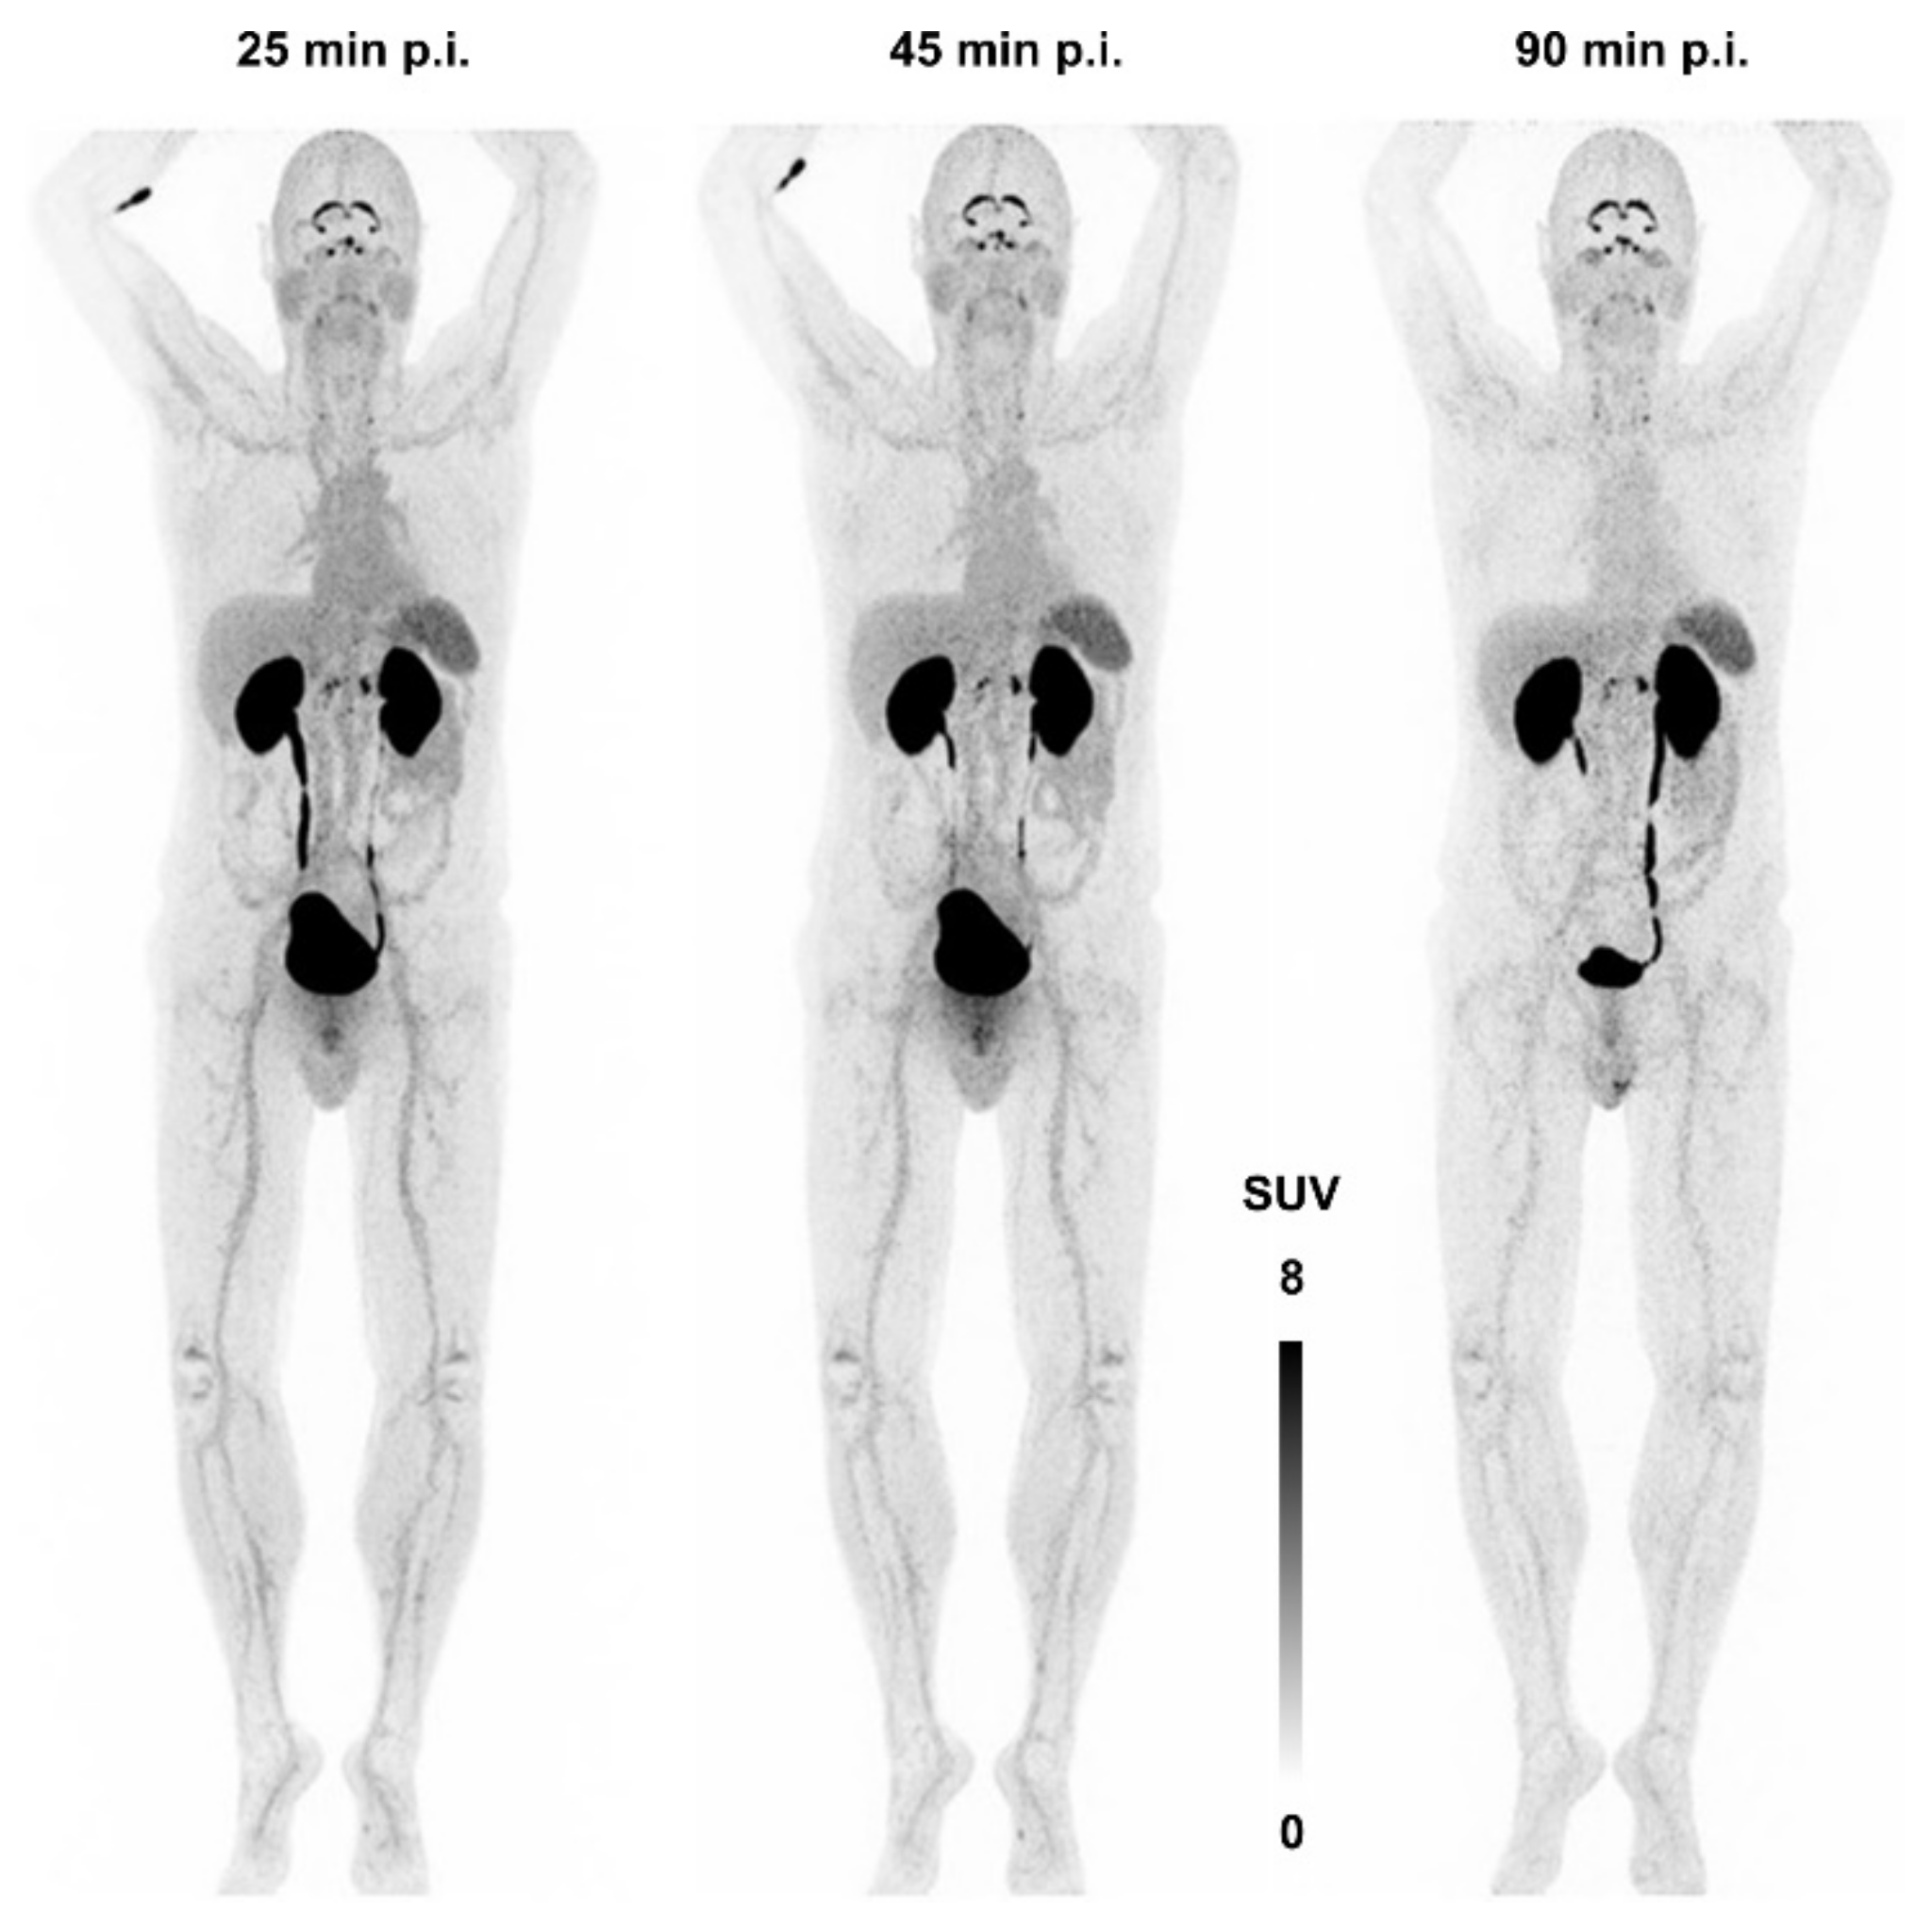

Figure 7 shows the first—and, currently, the only—αvβ8-integrin PET image acquired in human. There is apparently neither a strong specific nor a non-specific uptake in any major organ, apart from a strong signal in kidneys and bladder due to renal excretion. The notion of β8-integrin expression on neural cells (astrocytes) might nonetheless be connected to a substantial uptake in the plexus choroideus and -coeliacus [115]. However, due to a lack of pertinent immunohistochemistry data, no definitive statement can currently be made concerning this observation, and any conclusion would be premature. This situation is quite typical for the entire field of αvβ8-integrin imaging—many hypotheses are not yet supported with enough data and experience. It is nevertheless expected that the knowledge about the in vivo expression patterns of this integrin will substantially grow in the near future, because an imaging tool is now available.

Figure 7.

αvβ8-integrin PET imaging (maximum intensity projection) in human using 68Ga-Triveoctin. Copyright notice: Figure reprinted from EJNMMI Res. 2020, 10, 133. Quigley et al., Tracking a TGF-β activator in vivo: sensitive PET imaging of αvβ8-integrin with the Ga-68-labeled cyclic RGD octapeptide trimer Ga-68-Triveoctin [116]; under Creative Commons CC BY 4.0.